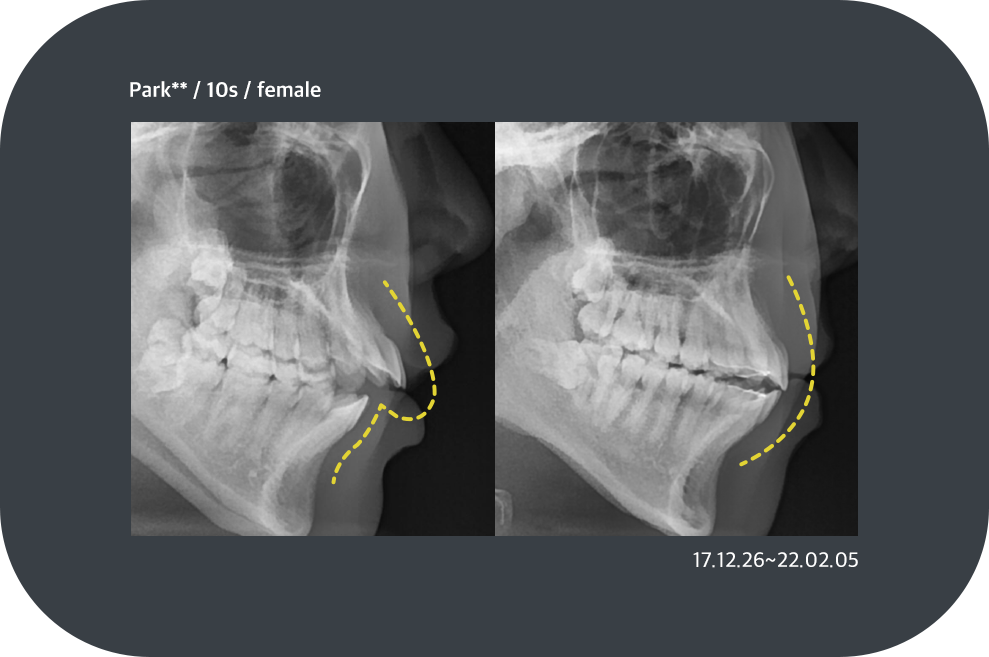

치료사례

치아교정 치료사례

ortho_case01

ortho_case02

ortho_case03

ortho_case04

*모든 증례 사진은 의료법 제23조, 제56조에 의거하여, 당사자의 동의하에 게시하였습니다.

*치료 사진은 모두 본원에서 치료한 환자분의 사진입니다.

*치료 사진은 모두 동일인의 사진이며, 동일조건에서 촬영하였습니다.

*개인의 차이에 따라 시술 및 수술 후 부작용이 발생할 수 있으며, 의료진과 충분한 상담을 받으시기 바랍니다.